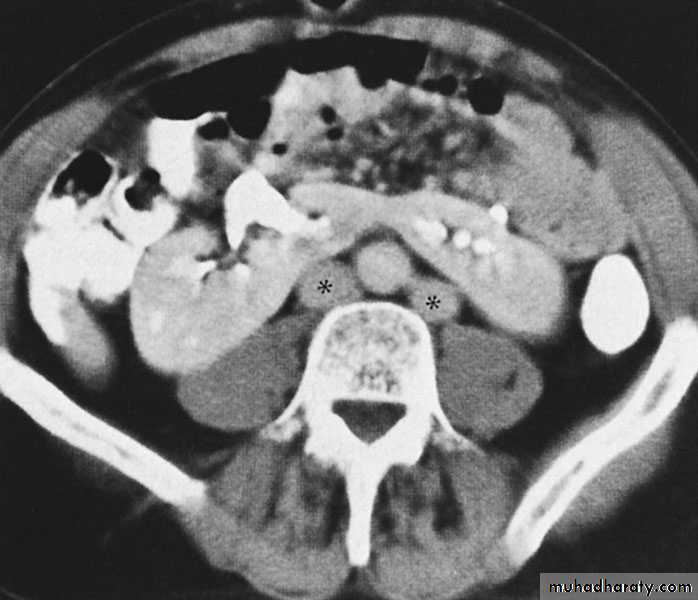

Diagnosis ultrasound, IVU, CT scan

Both kidneys replaced by large number of cysts of variable size which make the kidney of large size.

The cysts contain clear fluid but sometimes blood.

The cysts progressively increase in size causing pressure atrophy of the renal parenchyma and pressing the ureter.

U/S, IVU, CT scan, MRI